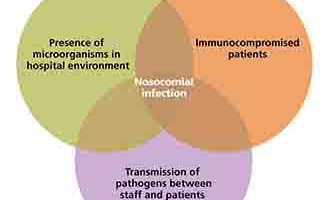

اسلاید 17: عفونت بیمارستانی (Nosocomial Infection):عفونتهــای جدیدی هستند که در زمان بستری شدن در بیمارستان ایجاد میشوند و گاه حتی بعــد از مرخص شدن بیمار خود را نشان میدهند.به عـبـارت دیگر، این عفونتها در زمان پذیرش بیمار وجود نداشتــه اند، بیمار در دوره کمون نبوده و در ادامــه عفونت ناشی از بستری قبلی نیز نبودهاند (و فقط به خاطر شرایط بیمارستان رخ میدهند)مثل: عفونتهای ادراری ناشی از سوند، عفونتهای بعد از عمـــــل جراحی و ...عفونت فرصت طلب (Opportunistic Infection):این عفونتها در زمینه اختلال ایمـنـــی بـه وجــــود میآینـــد.در حالت عادی (ایمنی طبیعی) بیماریزا نیستند.مانند تبخال، توکسوپلاسموز، سل و ...خصوصاً در ایدز رخ می دهند. چرا؟17